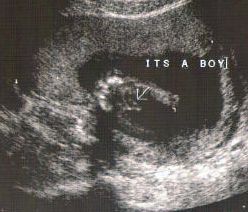

عکس جنین پسر در سونوگرافی هفته نوزدهم بارداری

همانطور که در شکل با نشانک مشخص شده است، در هفته نوزدهم بارداری آلت تناسلی بین پاها معلوم است. فرزند شما حالا نزدیک به 240 گرم وزن دارد و قدش به 15.3 رسیده است. او حالا اندازه یک انبه است.